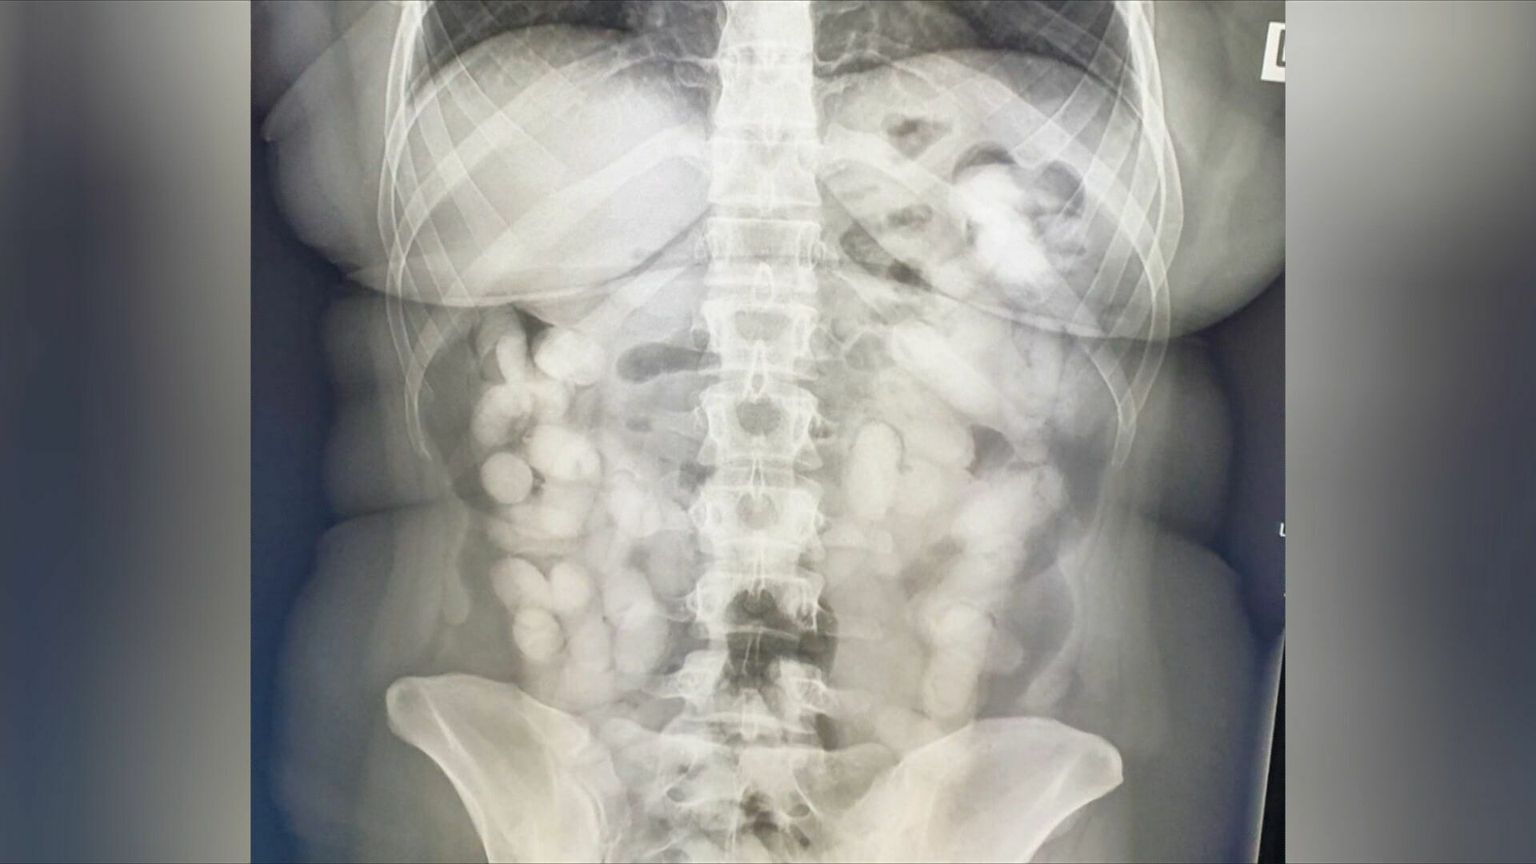

• U Zagrebu uhićena mula - 1 Foto: DNEVNIK.hr